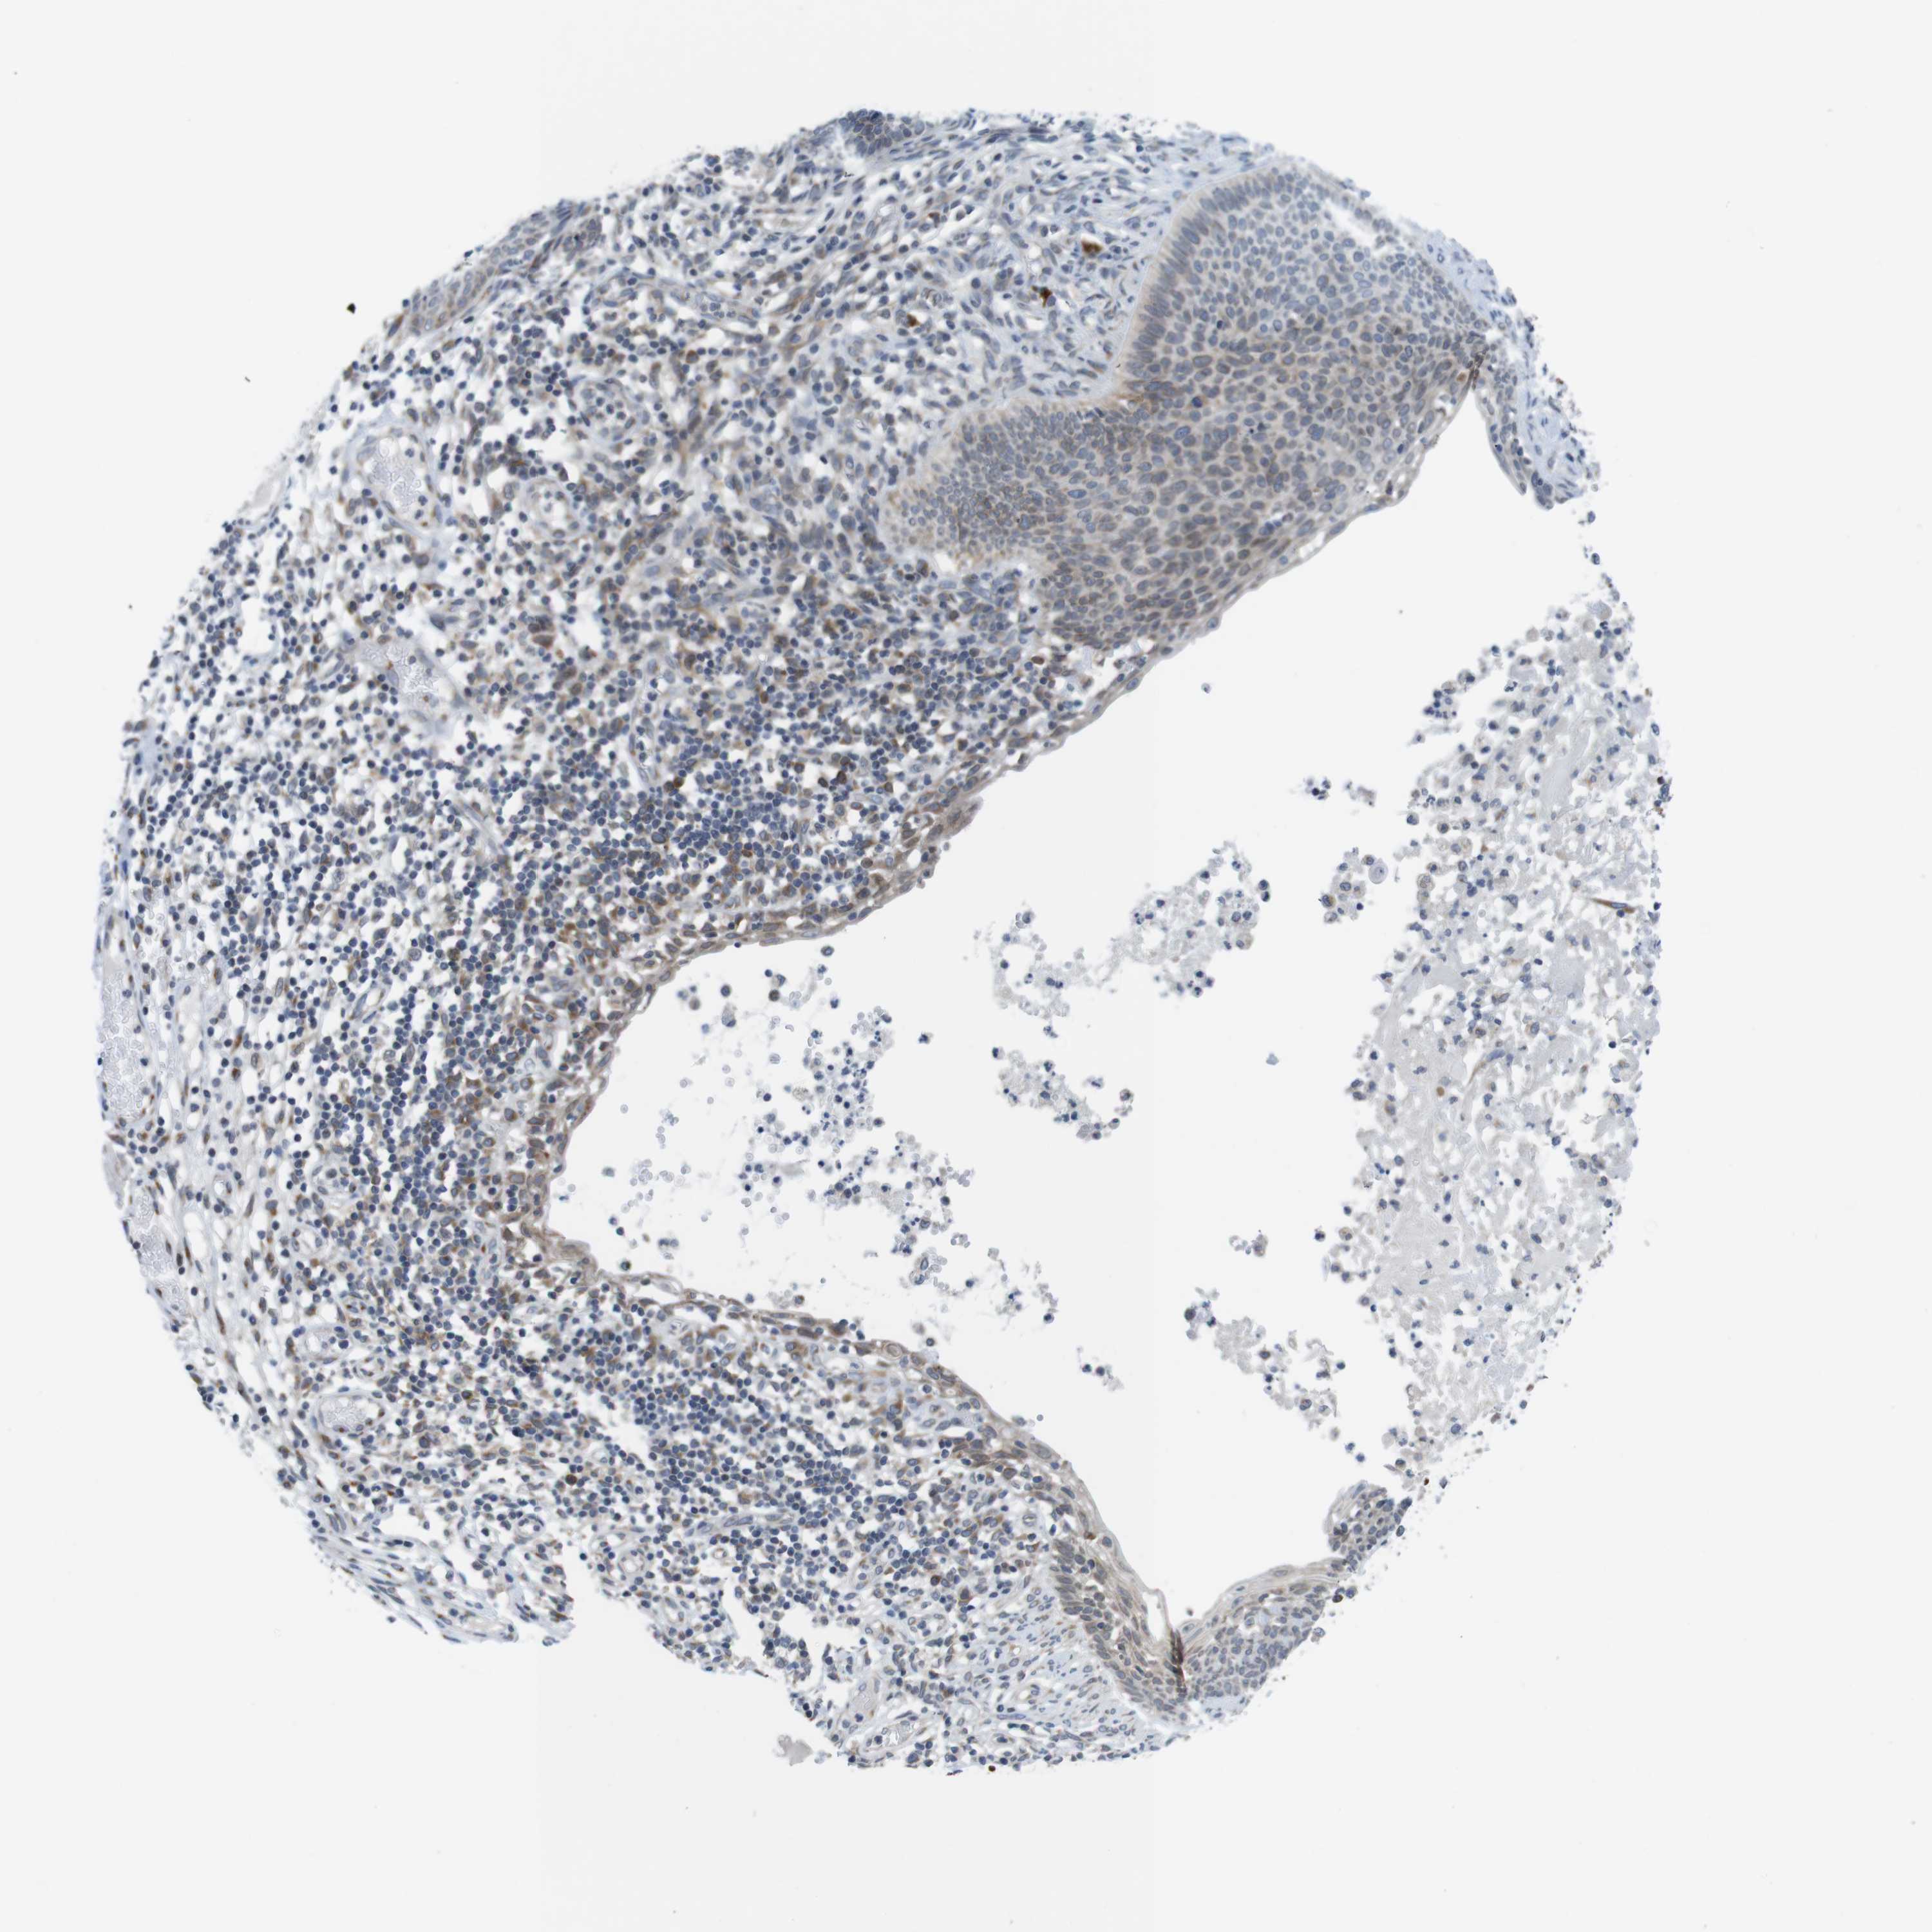

SKIN CANCER - Protein expressioni

A mouse-over function shows sample information and annotation data. Click on an image to view it in a full screen mode. Samples can be filtered based on level of antibody staining by selecting one or several of the following categories: high, medium, low and not detected. The assay and annotation is described here.

Each image is clickable and will lead to virtual microscopy that enables deeper exploration of all samples and also displays staining intensity scores, fraction scores and subcellular localization as well as patient and tissue information for each sample.

Antibody HPA015242

Squamous cell carcinoma, metastatic, NOS